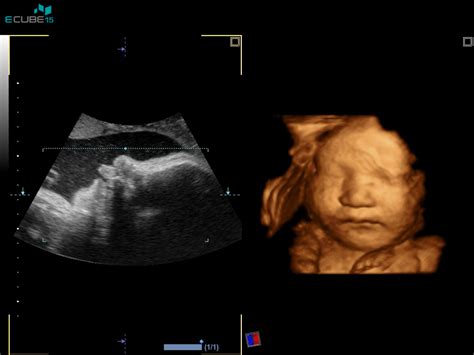

Do dopolnjenega 10. tedna nosečnosti je umetna prekinitev nosečnosti dovoljena na zahtevo nosečnice, brez navajanja posebnih razlogov. Postopek se začne pri osebnem ginekologu, ki izda napotnico za poseg. V kolikor nosečnica nima izbranega ginekologa, se lahko oglasi v najbližji ginekološki ambulanti. Ginekolog s pomočjo ultrazvoka potrdi nosečnost, izda napotnico za UPN ter po potrebi določi krvno skupino in opravi dodatne teste. Po opravljenem pregledu se nosečnica z napotnico naroči na poseg v katerokoli regijsko bolnišnico.

- Medicinske indikacije: To je najpogostejši razlog za odobritev posega po 10. tednu. Sodobna medicina omogoča odkrivanje razvojnih nepravilnosti z ultrazvokom (morfologija ploda v 20.-22. tednu) ali z invazivnimi testi, kot je amniocenteza. Če se ugotovi, da ima plod hudo telesno ali duševno okvaro (npr. Downov sindrom, srčne napake, okvare centralnega živčnega sistema), se lahko odobri prekinitev. Prav tako se prekinitev odobri, če bi nadaljevanje nosečnosti resno ogrozilo življenje ali zdravje nosečnice. To vključuje poslabšanje kroničnih bolezni (srčne napake, bolezni ledvic, rakava obolenja, ki zahtevajo takojšnje zdravljenje s kemoterapijo) ali akutna stanja, ki se pojavijo med samo nosečnostjo (npr. huda preeklampsija).